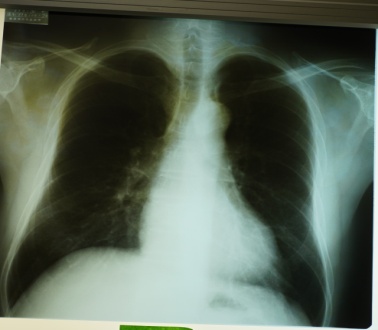

3. 初回XP胸膜プラーク無・CT有7名(30.4%)平均年齢73.4(66~80)歳【写真2】

【写真2】初回XP胸膜プラーク(-)初回CT胸膜プラーク(+)

胸部X線写真で胸膜プラークのある場合、胸膜プラークは経年的に厚く大きくなり徐々に石灰化した【写真1】。胸膜プラークはCTで66~80歳で初めて認められ、70台,80才の胸部CT写真撮影の必要性が認められた【写真3】。高濃度石綿ばく露をうけた23名中4名に80台でも胸部CTで胸膜プラークのない群が確認された。肺がんによる死亡が3名に認められ、胸膜プラーク有は1名で2名はXP・CT共に最後までプラークなしだった。職業性石綿ばく露を受けた集団は、退職から永眠までの期間の健診体制を必要とし、胸部X線CT写真を併用し観察する意義が再確認された5)